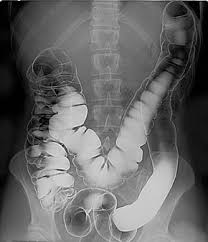

Double Contrast Barium Enema Wikipedia